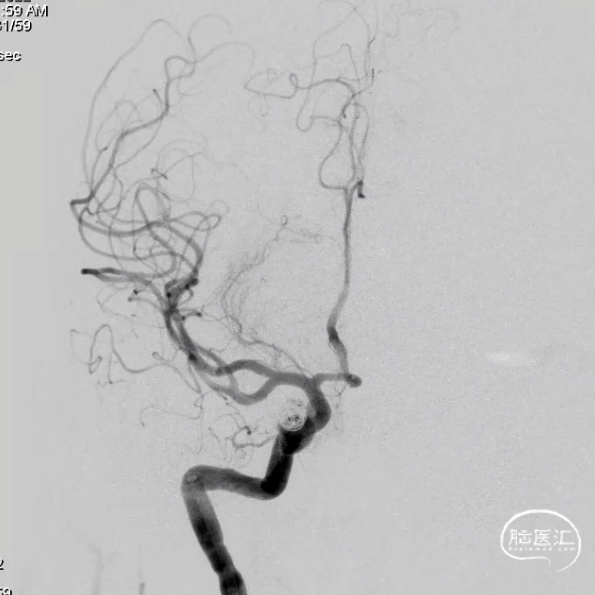

术后6个月造影随访提示动脉瘤完全愈合,载瘤动脉通畅。

4、该病例即刻造影显示血流重构满意,瘤腔内血流明显淤滞。术后六个月及12个月随访,均显示动脉瘤愈合,载瘤动脉通畅无狭窄。